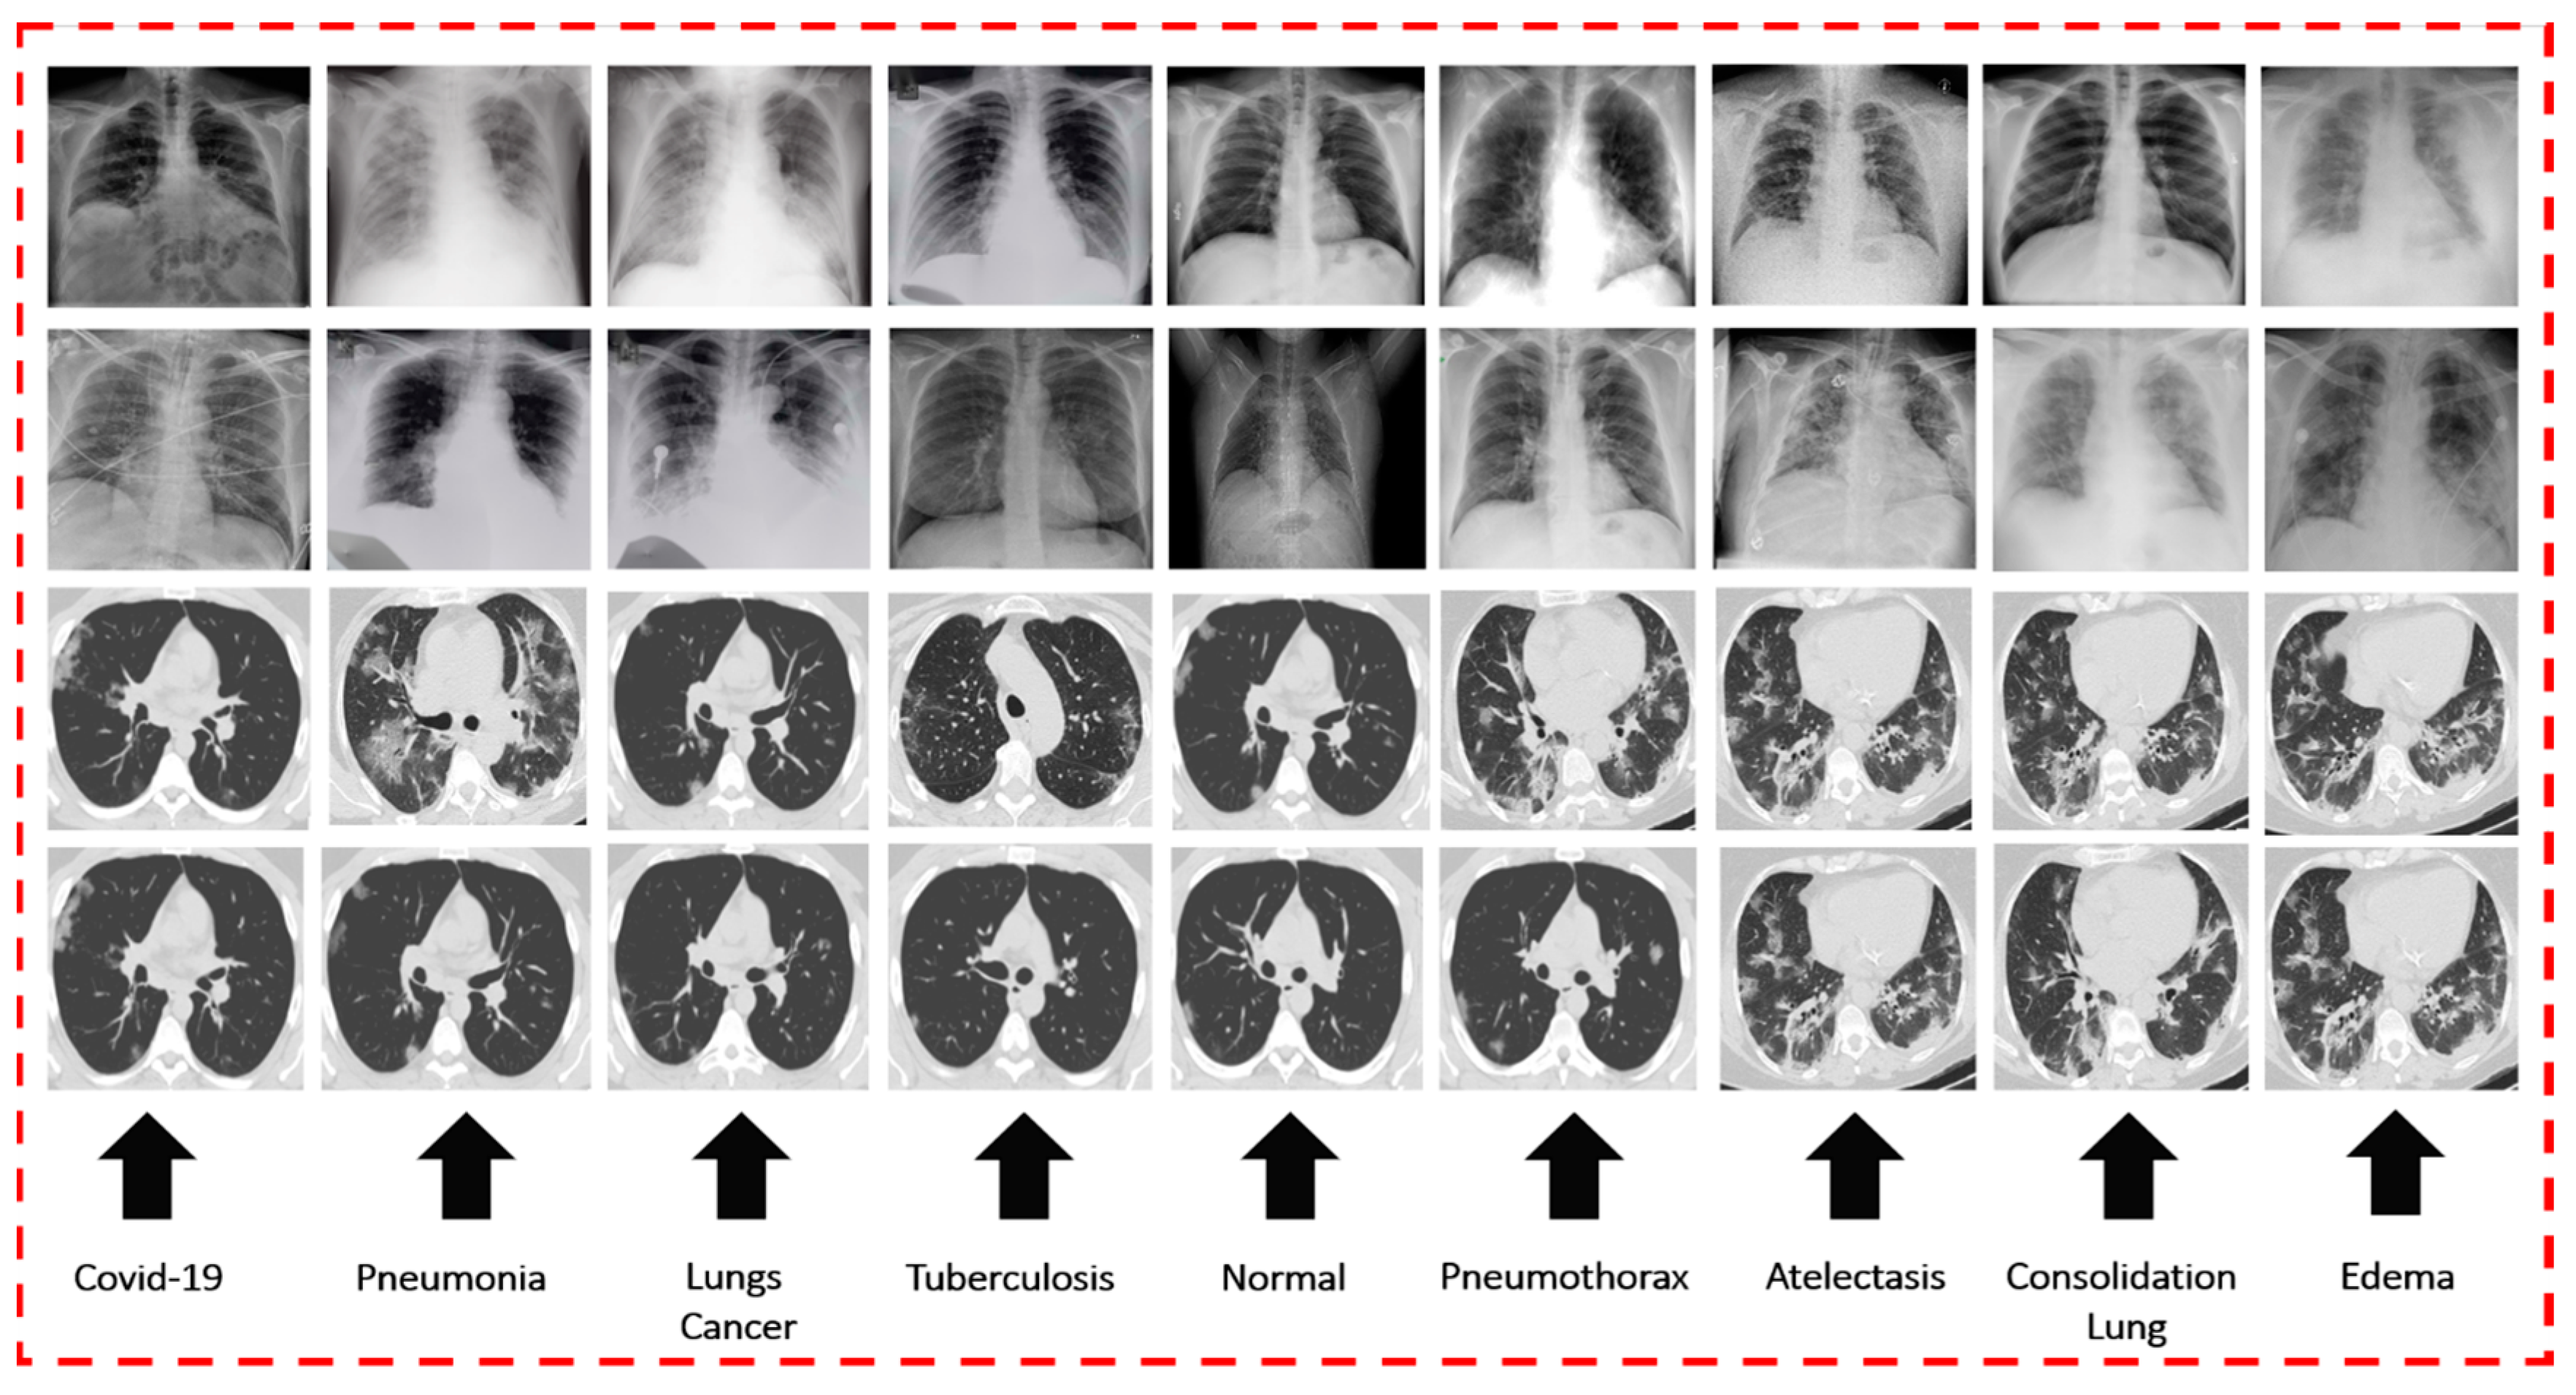

For training and verifying the models of DL via CXR, seven publicly accessible datasets on a variety of chest diseases were obtained from a large number of different sources. Initially, we gathered 423 chest radiographs of COVID-19 infections from Mendeley [56] and GitHub [57] sources. The chest radiographs of normal or healthy individuals were obtained from two datasets, namely, NIH [58] and Kaggle [59] chest radiographs. The images of pneumonia were obtained from the RSNA [60]. These datasets include 247 images of normal X-rays and 189 images of pneumonia X-rays. A total of 931 X-ray images were collected from the NIH [61], which were categorized as follows: 425 images of PNEUTH, 154 images of ATE, 198 images of EDE, and 154 images of COL. The remaining CXR images from the NIH dataset were excluded from this study. The dataset of lung cancer was taken from [62], and 74 CXR images were obtained from the dataset. Last, a total of 259 CXR images of patients diagnosed with TB were collected [63]. Figure 2 shows a sample image of COVID-19 as well as other chest diseases on CXR and CT scans.

Figure 2.

CT scan and CXR sample images of nine chest diseases.